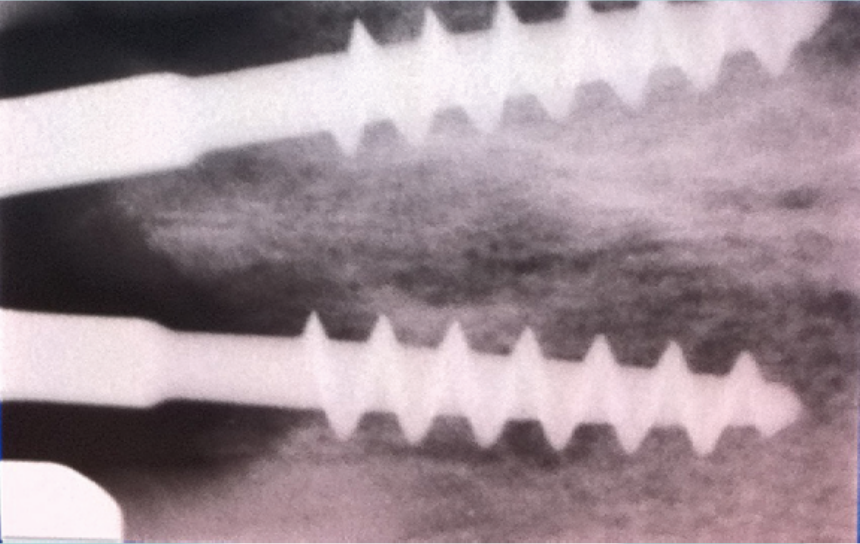

In our clinics we use since 1987 a technique called "immediate load implantology", which follows the protocols of the Italian School of Implantology, established more than 50 years ago.

This technique allows allows to use right away the implants inserted into the bone, by using temporary teeth made on the same day.

- The possibility of executing the implants even with the presence of reduced bone tissue thanks to the particular conformation of the implant (long and thin neck, large spirals)

- Better structural resistance of the implants in order to weld them together with a plank (electro-welded technique)

- Use of the bone in all its extension and where it is present

We have the adequate experience to confirm that, since the first implants that were implanted over 30 years ago have, with our satisfaction, remained in place and working. In addition, and not least, this technique allows a significant cost reduction.

implantologia_di_scuola_italiana_13122019_120713.png